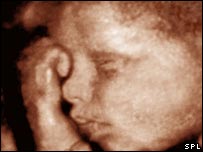

'Ultra-sonografia para recordação' deve ser evitada, diz revista

Ultra-sonografia em 3D

Pais britânicos pagam até mais de R$ 1 mil para ter exame 'de recordação'

Ultra-sonografias tradicionais - as mais comuns na rede pública - são bidimensionais e os pais levam para casa imagens sem muita definição, em preto e branco.

Mas as companhias comerciais britânicas estão oferecendo as novas imagens, em 3D, e até mesmo pequenos filmes, com os movimentos da criança.

Em seu artigo, o médico Geoff Watts afirma que os futuros pais que querem levar para casa um CD ou DVD com este exame pagam entre 150 e 250 libras(entre R$ 624 e R$ 1040).